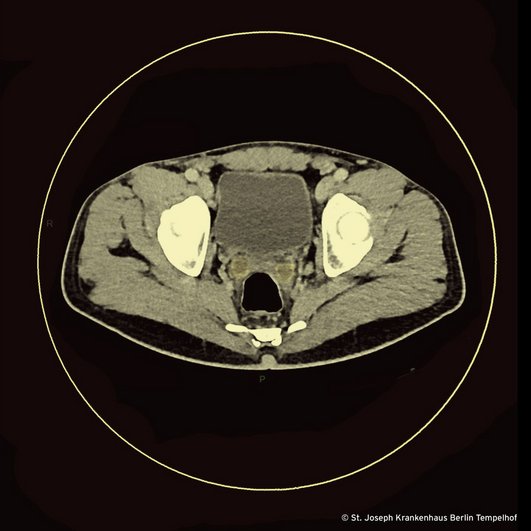

Weil wir unserem Patienten die Entfernung seines verbleibenden Hodens zum Zweck der Materialgewinnung ersparen wollten, haben wir mittels Bildgebung nach extragenitalen Manifestationen einer Tuberkulose gesucht, aber keine gefunden. Die Samenbläschen, die Sie in unserem CT-Bild sehen wiesen jedoch Abszedierungen auf, weshalb wir optimistisch waren, die Verdachtsdiagnose „TB“ aus alternativem Probenmaterial erzwingen zu können: Zuerst fokussierten wir uns auf den Urin, wo allerdings weder mikroskopisch noch molekularbiologisch der Nachweis von säurefesten Stäbchen bzw. M. tuberculosis Komplex gelang. Dann baten wir den Patienten um eine Spermaprobe. Und weil wir uns unserer Sache so sicher waren, verletzten wir die goldenen Regeln der Präanalytik. Die Quittung kam am selben Tag in Form des folgenden Befundes: